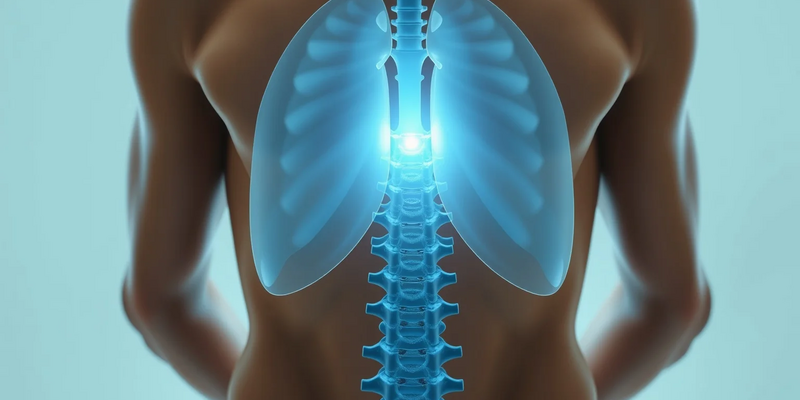

Das Zwerchfell ist mehr als nur Atemmuskel – es ist ein zentraler Stabilisator. Anatomisch ist es direkt mit den oberen Lendenwirbeln verbunden. Jede Verspannung des Muskels wirkt sich daher unmittelbar auf die Wirbelsäule aus.

Bei einer tiefen Einatmung senkt sich das Zwerchfell ab. Es arbeitet dabei mit der quer verlaufenden Bauchmuskulatur und dem Beckenboden zusammen. Dieses Zusammenspiel erhöht den Druck im Bauchraum.

- Es entsteht ein natürliches Korsett, ein „innerer Airbag“.

- Dieser Druck stabilisiert die Lendenwirbelsäule von vorne.

- Bandscheiben und Wirbelgelenke werden entlastet.